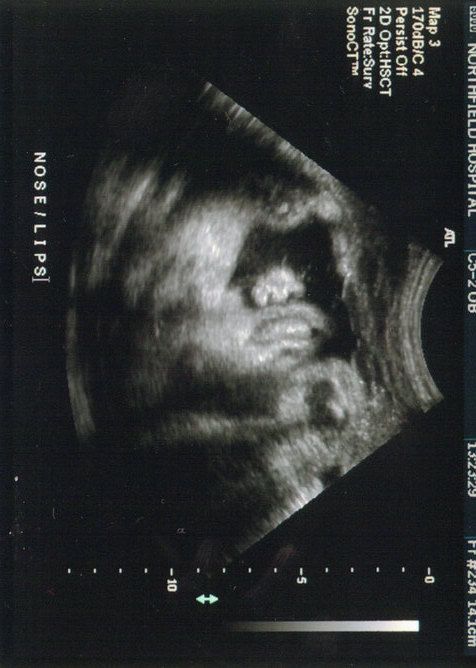

Here is my Miss Alyssa. Look at her chubby face!!!

srry it's kind of big! But it's so cute!!

5littleladies replied: I forgot to mention-If you look closely you can see she has her arm draped over her forehead, kind of in a "woah is me" type of gesture. And yes, it does look like that is her tongue. What a stinker.

coasterqueen replied: I was just going to say it looked like her arm over her face and her tongue out. What a precious pic!!!